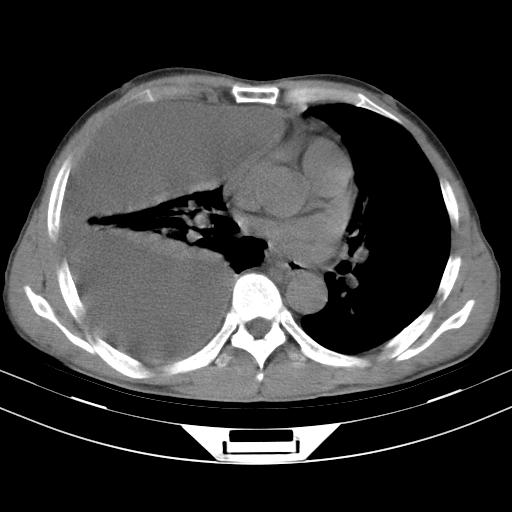

男性,44岁,结核病史多年。现胸闷气短,咳嗽,偶咳血。

1)两肺继发性肺结核伴空洞形成,左肺多发性结核球。2)右侧大量胸腔积液伴右肺部分膨胀不全。3)纵隔淋巴结肿大。

1,双肺多发结节 并空洞影改变, 左侧胸腔积液并部分包裹, 结合原病史首先考虑结核. 但也不除外其它.

吉大一院胸水抽检结果:结核性胸水